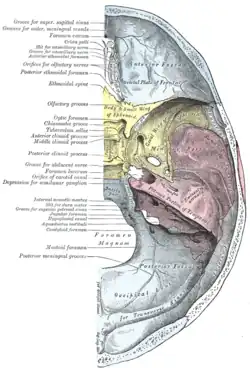

Articulação da mandíbula. Aspecto lateral. Base do crânio. Superfície superior.

Base do crânio. Superfície superior. Ossos esfenoides e temporais.

Ossos esfenoides e temporais. Arco zigomático.